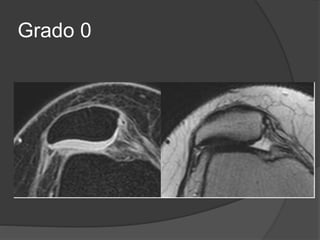

Condromalacia

 El grado se determina por artroscopía.

 Grado 0: Normal.

 Grado 1: Reblandecimiento del cartílago.

 Grado 2: Ulceración poco profunda, menor del 50% del espesor.

 Grado 3: Ulcera profunda, mayor del 50% del espesor, pero que

no se extiende al hueso.

 Grado 4: Ulcera con exposición del hueso subcondral.

Grado 0